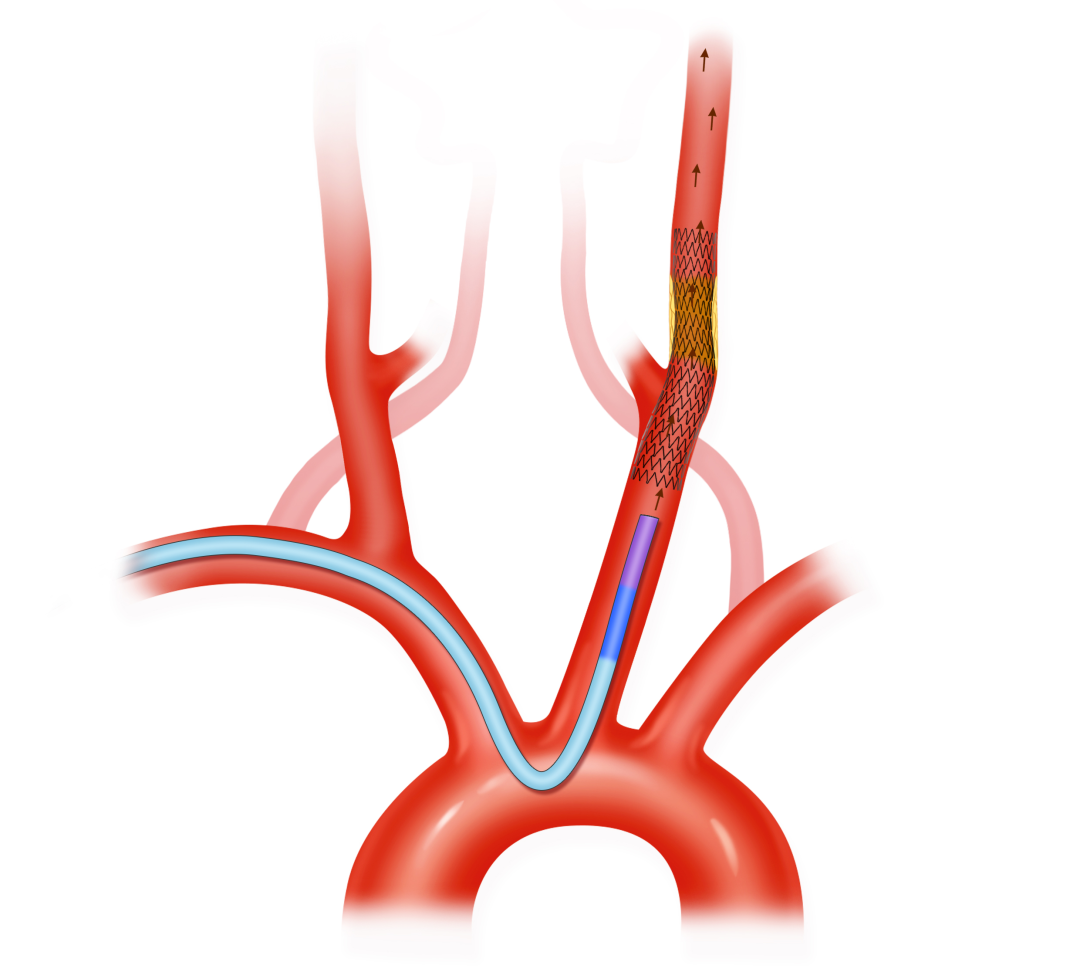

支架输送和释放

支架输送至最下端转折处时,需要保持一个持续缓慢的推力,时刻注意下坐的趋势,推拉结合, 随时调整张力;

如果下坐趋势明显,在预扩充分的前提下,可以上推DA越过狭窄处,尽量上高至保护伞下缘,利用木马技术输送支架,尤其左颈;

右侧由于有头臂干分叉作为支撑, 下坐可能性较左侧小,往往不需要上推DA。

然后后退DA,留出支架释放空间,释放支架。